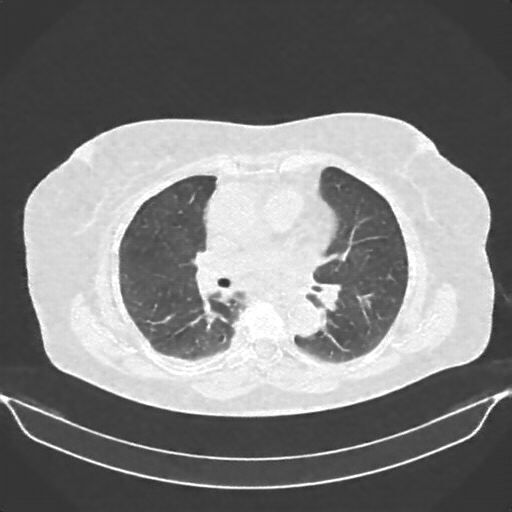

Targeted Slice 70 - Lung Window Analysis (Generated vs Real Venous)

0.660

Lung SSIM

118.4

Lung RMSE

51.5

Lung MAE

Average Lung Window Metrics Across All Slices (161 slices) - Generated vs Real Venous

0.663

Lung SSIM (Avg)

109.6

Lung RMSE (Avg)

49.1

Lung MAE (Avg)

Reconstructed NATIVE CT scan (cycle consistency)

No window - Raw intensity values

Lung window (WL -600, WW 1500 β†’ Low βˆ’1350, High +150)